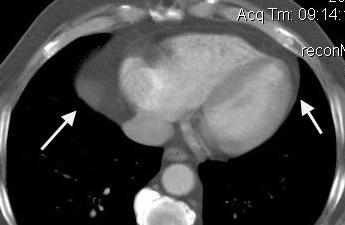

La ocupación del espacio pleural por derrame (o obstrucción aérea) se acomoda con expansión aumentada de la caja torácica, especialmente en eje vertical. La consecuencia es aplanamiento e incluso inversión diafragmática.

Afzal S, Fatima K, Ambareen M. Antenatal ultrasound diagnosis of congenital high airway obstruction syndrome: a case report and review of literature. Cureus. 2019. Thoma R et al. Physiology of breathlessness associated with pleural effusions. Curr Opin Pulm Med. 2015

Wang JS et al. Changes in pulmonary mechanics and gas exchange after thoracentesis on patients with inversion of a hemidiaphragm secondary to large pleural effusion . Chest 1995

Mesotelioma epitelioide